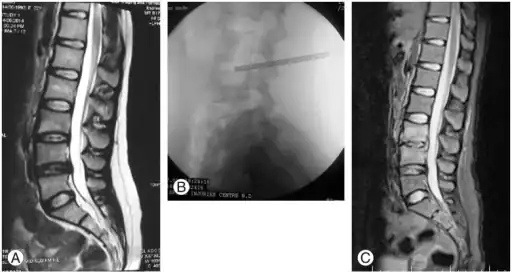

- MRI

Diagnosis

- Radiographs of the spine

- – Radiographic changes associated with Pott disease present relatively late. These radiographic changes are characteristic of spinal tuberculosis on plain radiography:

- Computed tomography of the spine